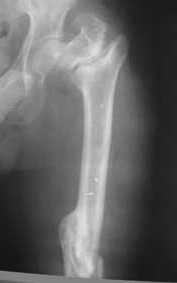

Leonid Solomin 03 Март 2009, 22:07

Уважаемый Попов Виктор!

Возможно, пример (в приложении) поможет Вам определиться с выбором тактики лечения (у нашего пациента, кроме тугого ложного сустава вертельной области, сложная деформация н/3 бедренной кости; т.к. это не имеет значения к обсуждаемой теме - оставил "за кадром"). Как Вы видите, мы в данном случае не вводили чрескостные элементы в зону установки имплантата. При отказе от наложения опоры на таз (кстати, она не обязательно может быть громоздкая спицевая; арки со стержнями-шурупами, введенными в крыло подвздошной вполне достаточно) "не удивляйтесь", если опора со стержнями-шурупами, введенными в вертельной области в скором времени дестабилизируется, возникнет воспаление мягких тканей у чрескостных элементов. Такая опора "имеет на это право": нагрузка конечности от вершины дистального фрагмента до кончиков пальцев ляжет на нее. А двух-трех введенных рядом стержней-шурупов, как их не разноси от фронтальной плоскости, в данном

случае явно недостаточно для адекватной фиксации. + для того, чтобы выбрать оптимальные чрескостные элементы для промежуточной и дистальной опор, можете воспользоваться атласом

В приложении пример пациента, близкого по картине к тому, что представил Виктор (варус и смещение периферического отломка на поперечник кзади). Сделали как раз то, что Виктор исходно намеревался - аппаратная коррекция и затем гамма.